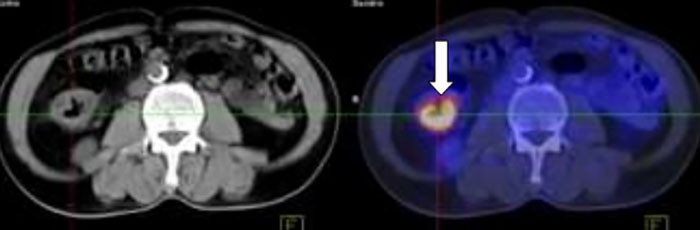

Nội soi đại tràng cho bệnh nhân, các bác sĩ nhận thấy có khối sùi vào lòng đại tràng phải. Bà H. được tiến hành bấm sinh thiết cho kết quả ung thư biểu mô tuyến đại tràng phải, di căn hạch ổ bụng, di căn gan, phổi. Người bệnh được điều trị bằng phác đồ kết hợp kháng thể đơn dòng và hóa trị.

Hình ảnh khối u đại tràng phải, kích thước 3x4cm của bệnh nhân H.

Sau 6 chu kỳ hóa trị kết hợp Bevacizumab, các tổn thương u nguyên phát, di căn hạch ổ bụng, nốt di căn phổi đã không còn, chất chỉ điểm khối u CA 19-9 giảm. Tuy nhiên tổn thương di căn gan vẫn tồn tại và kích thước tổn thương gan đã thuyên giảm. Bệnh đáp ứng một phần với điều trị.